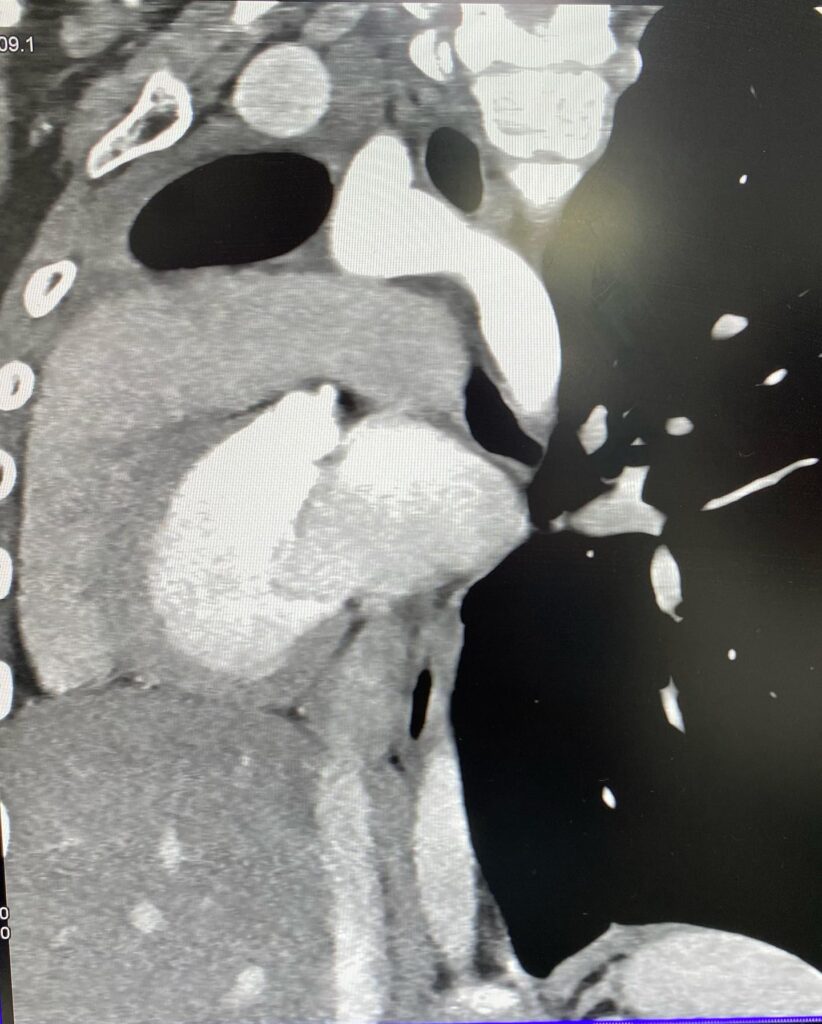

Արդյունքը տպավորիչ էր։ Երեխայի մոտ առկա էր աջ թոքի ագենեզիա (թոքը չի զարգացել, համապատասխանաբար բացակայում էին նաև աջ գլխավոր բրոնխը, աջ թոքային զարկերակը և աջ թոքային երակները), ինչի հետևանքով միջնորմը (այդ թվում սիրտը) տեղակայված է կրծքավանդակի աջ կեսում։

Սրտի նման տեղակայումը հեմոդինամիկ շեղումներ չի առաջացրել. երեխան ունի կառուցվածքային առողջ սիրտ։